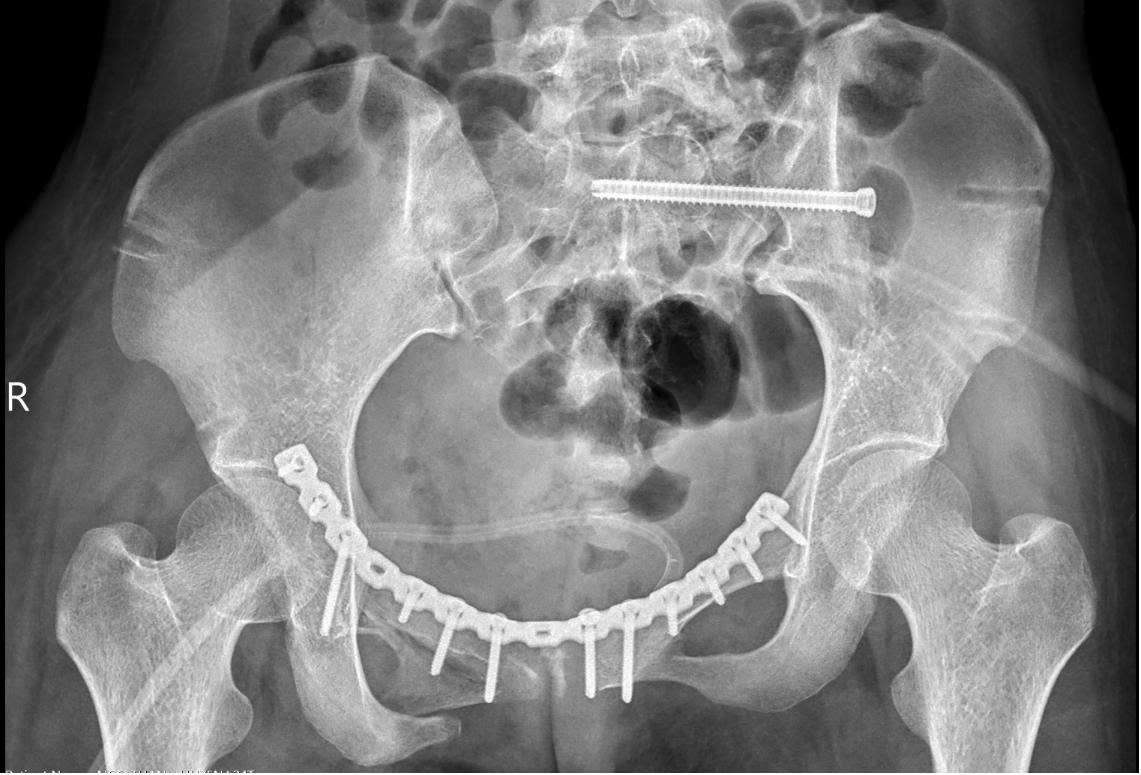

Các bác sĩ đánh giá, hội chẩn tình hình của bệnh nhân (trái) cùng hình ảnh chụp Xquang xương chậu của bệnh nhân (phải)

Hình ảnh chụp Xquang của bệnh nhân sau phẫu thuật